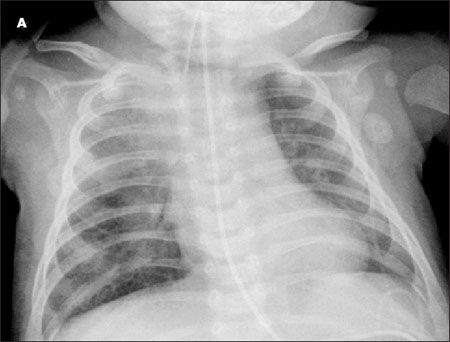

A chest radiograph from a baby girl with a history of difficulty in breathing showed a hyperinflated right lung with a shift of the mediastinal contents into the left hemithorax (A). A chest CT scan showed diffuse mediastinal and right hilar adenopathy (B). The case emphasizes the difficulty in diagnosing pulmonary tuberculosis in an infant with a nonspecific presentation and no travel or contact history.

Image courtesy of Mansi B. Mehta, MD, Christopher Young, MD, and Sharda Udassi, MD.